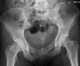

Familial pubic diastasis

Defective pubic ossification